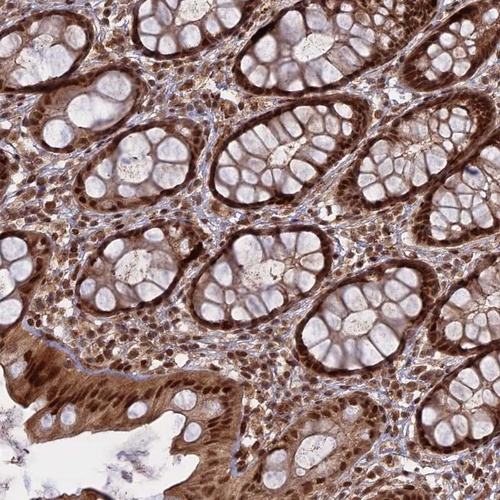

Immunohistochemical staining of human rectum shows strong nuclear positivity in glandular cells.